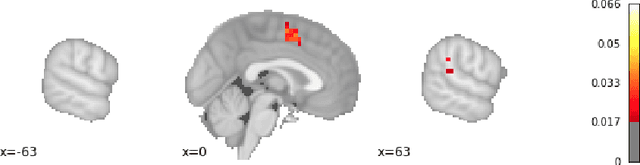

Abstract:With the growing number of published functional magnetic resonance imaging (fMRI) studies, meta-analysis databases and models have become an integral part of brain mapping research. Coordinate-based meta-analysis (CBMA) databases are built by automatically extracting both coordinates of reported peak activations and term associations using natural language processing (NLP) techniques. Solving term-based queries on these databases make it possible to obtain statistical maps of the brain related to specific cognitive processes. However, with tools like Neurosynth, only singleterm queries lead to statistically reliable results. When solving richer queries, too few studies from the database contribute to the statistical estimations. We design a probabilistic domain-specific language (DSL) standing on Datalog and one of its probabilistic extensions, CP-Logic, for expressing and solving rich logic-based queries. We encode a CBMA database into a probabilistic program. Using the joint distribution of its Bayesian network translation, we show that solutions of queries on this program compute the right probability distributions of voxel activations. We explain how recent lifted query processing algorithms make it possible to scale to the size of large neuroimaging data, where state of the art knowledge compilation (KC) techniques fail to solve queries fast enough for practical applications. Finally, we introduce a method for relating studies to terms probabilistically, leading to better solutions for conjunctive queries on smaller databases. We demonstrate results for two-term conjunctive queries, both on simulated meta-analysis databases and on the widely-used Neurosynth database.